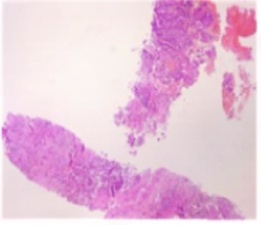

2024-11-29行肺穿刺活检。

病理诊断:(肺组织)穿刺组织镜下示:浸润性癌,待免疫组化检查进一步明确。本院病理B2462910免疫组化结果:(肺组织)肿瘤细胞:CK-L(+),CK7(+),CK20(-),NapsinA(+),TTF-1(+),CDX-2(-),CK5/6(灶散+),P63(散+),P40(-),Syn(-),CgA(-),BRG1(+),INI-1(+),Ki67(热点区约20%+):结合HE切片,本例符合:腺癌,肺来源免疫表型改变,少量肿瘤细胞伴鳞状上皮标记表达。

基因检测:检出I类变异LINC00707(Intergenic)-ALK(Exon20-29)。